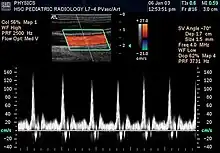

Échographie Doppler

L'échographie Doppler est un examen médical échographique en deux dimensions non invasif qui permet d'explorer les flux sanguins intracardiaques et intravasculaires. Elle est basée sur un phénomène physique des ultrasons : l'effet Doppler. Elle est souvent surnommée écho Doppler.

L’échographe Doppler est constitué d’un échographe classique couplé à une sonde Doppler.

Lorsqu'un faisceau d'ultrasons traverse les cavités cardiaques ou les vaisseaux, l’écho renvoyé par les éléments figurés du sang (qui deviennent des émetteurs) aura une longueur d'onde plus longue (son plus grave) s'ils s'éloignent du capteur ; et une longueur d'onde plus courte (son plus aigu) s'ils se dirigent vers le capteur.

La sonde Doppler recueillera donc un écho dont la fréquence (longueur d'onde) sera différente de la fréquence d'émission.

La différence des fréquences d'émission (F) et de réception (F'), F - F', permet de calculer la vitesse et la direction des globules rouges.

Les échographes Doppler actuels permettent un codage couleur des flux sanguins. Par convention, les flux positifs qui s'approchent de la sonde sont codés en rouge, les flux qui s'en éloignent sont codés en bleu. Il permet ainsi une visualisation directe des flux sanguins qui se superposent à l'image en échographie bidimensionnelle en échelle de gris.